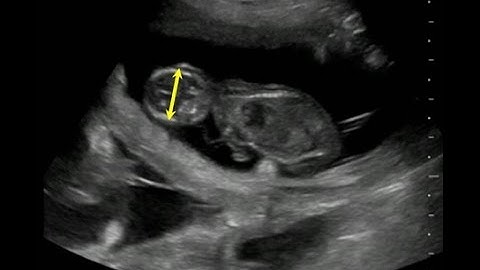

How to calculate gestational age in felines using biparietal (head) diameter